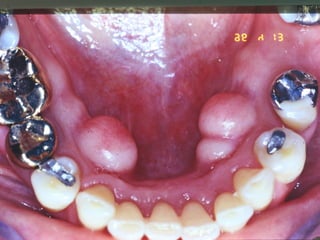

Torus

• Mandibular

• Paltino

• Etiologia